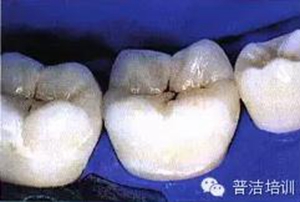

十六、最終的修復(fù)體,是不是很漂亮

修復(fù)后一周復(fù)查